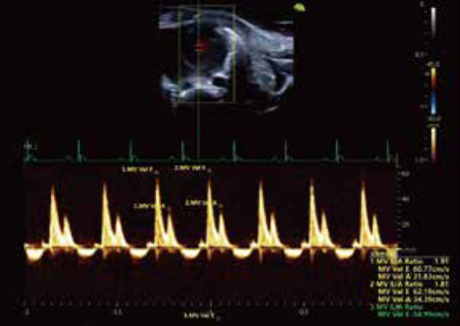

• マウス僧帽弁血流スペクトル

D10 LAB は高い時空間解像度30μm, 500fpsを可能にしたポータブルタイプの超音波イメージングシステムのハイエンドモデルです。 ポータブルタイプでは世界トップクラスの性能を有し, マウス心機能の解析や小動物の体内を繊細に観察・測定できます。

ECG入力機能やストレインイメージング機能を標準搭載して, マウスの心機能検査のために開発されたモデルです。組織速度イメージング(TVI)機能, マルチゲートドプラ, マイクロバブルを併用するコントラストエコー機能, エラストグラフィ(SE) をオプションで追加することが可能です。